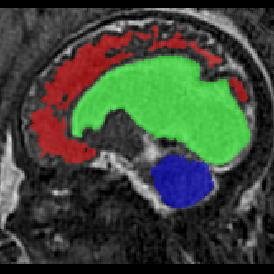

Limiting failures of machine learning systems is of paramount importance for safety-critical applications. In order to improve the robustness of machine learning systems, Distributionally Robust Optimization (DRO) has been proposed as a generalization of Empirical Risk Minimization (ERM). However, its use in deep learning has been severely restricted due to the relative inefficiency of the optimizers available for DRO in comparison to the wide-spread variants of Stochastic Gradient Descent (SGD) optimizers for ERM. We propose SGD with hardness weighted sampling, a principled and efficient optimization method for DRO in machine learning that is particularly suited in the context of deep learning. Similar to a hard example mining strategy in practice, the proposed algorithm is straightforward to implement and computationally as efficient as SGD-based optimizers used for deep learning, requiring minimal overhead computation. In contrast to typical ad hoc hard mining approaches, we prove the convergence of our DRO algorithm for over-parameterized deep learning networks with ReLU activation and a finite number of layers and parameters. Our experiments on fetal brain 3D MRI segmentation and brain tumor segmentation in MRI demonstrate the feasibility and the usefulness of our approach. Using our hardness weighted sampling for training a state-of-the-art deep learning pipeline leads to improved robustness to anatomical variabilities in automatic fetal brain 3D MRI segmentation using deep learning and to improved robustness to the image protocol variations in brain tumor segmentation. Our code is available at https://github.com/LucasFidon/HardnessWeightedSampler.